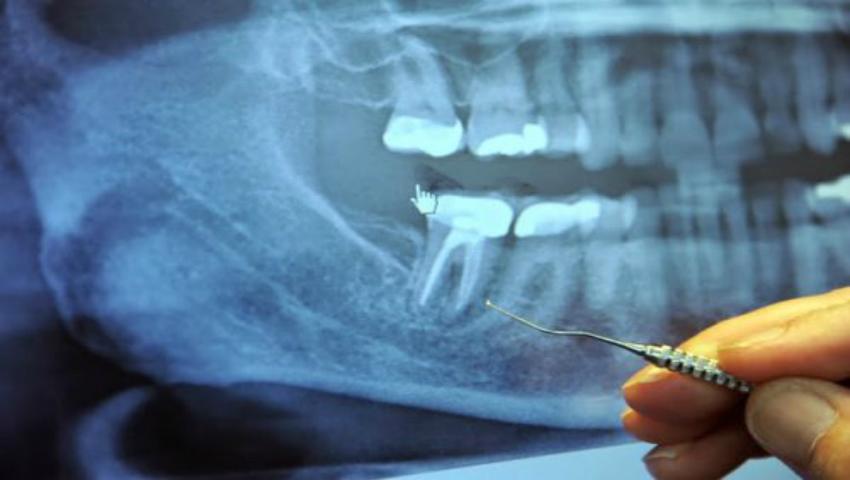

Un medic german susţine că 97% dintre pacienţii cu cancer în stadiul terminal au apelat la proceduri de obturaţie dentară, iar legătura dintre cancer şi o astfel de procedură ar exista. Care sunt afirmaţiile specialistului?

În fiecare zi, doar în SUA, au loc 41000 de proceduri de obturaţie dentară a canalului radicular. În esență, dinții fără nerv sunt dinți “morți”, care pot deveni “incubatoare tăcute” în care se dezvoltă în voie bacterii anaerobe extrem de toxice; aceste bacterii, în anumite condiții, își croiesc drum către fluxul sangvin și pot provoca o serie de boli care nu sunt semnalate decât după câteva decenii. Majoritatea acestor dinți toxici arată și dau senzația că sunt în regulă timp de mai mulți ani, ceea ce face ca rolul lor în boala sistemică să fie chiar mai greu de determinat în istoricul medical al pacientului. Din păcate, majoritatea medicilor stomatologi nu își dau seama de potențialele riscuri pentru sănătate la care își expun pacienții, raportează un articol publicat pe realfarmacy.com.Specialiștii atrag atenția asupra riscurilor pe care le implică această procedură aparent de rutină. Organismele microscopice se deplasează constant în jurul canalelor dentare. Atunci când dentistul face procedura de obturație a canalului radicular, el golește dintele, adică îndepărtează pulpa dintelui afectată, iar camera pulpară este și ea curățată, apoi umple camera pulpară cu un material numit gutaperca, ca să oprească alimentarea cu sânge de la dinte, astfel încât acesta să nu mai circule prin dinte.Dar rămâne labirintul de mici canaliculi. Iar bacteriile, din moment ce li s-a tăiat sursa de hrană, se ascund în aceste tunele unde sunt în siguranță și foarte bine protejate de antibiotice și răspunsul pe care l-ar putea avea sistemul imunitar. Aceste bacterii se transformă, în lipsa oxigenului și a hranei, în bacterii anaerobe, care pot produce o varietate de toxine periculoase.Potrivit aceluiași articol,  se pare că există o conexiune între cancer și obturația radiculară. Dr. Robert Jones, un cercetător care a studiat relația dintre canalele radiculare și cancerul la sân, a găsit o legătură extrem de mare între cele două. El susține că a găsit următoarea corelație într-un studiu ce a durat 5 ani, făcut pe 300 de cazuri ale unor paciente ce sufereau de cancer la sân: 93% dintre femeile cu cancer la sân au avut o procedură de obturație a canalului radicular; 7% dintre ele au avut o altă patologie orală; tumorile, în majoritatea cazurilor, au apărut pe aceeași parte a corpului pe care a fost efectuată obturația sau obturațiile de canal sau celelalte patologii orale.Dr. Jones susține că toxinele produse de bacteriile de la un dinte infectat sau de la maxilar sunt capabile să inhibe acele proteine care, în mod normal, suprimă dezvoltarea tumorilor. Un alt medic german a raportat rezultate similare. Dr. Josef Issels arată că, în cei 40 de ani în care a tratat pacienţii bolnavi de cancer în faza terminală, 97% dintre pacienții săi bolnavi de cancer, avuseseră obturație de canal radicular.